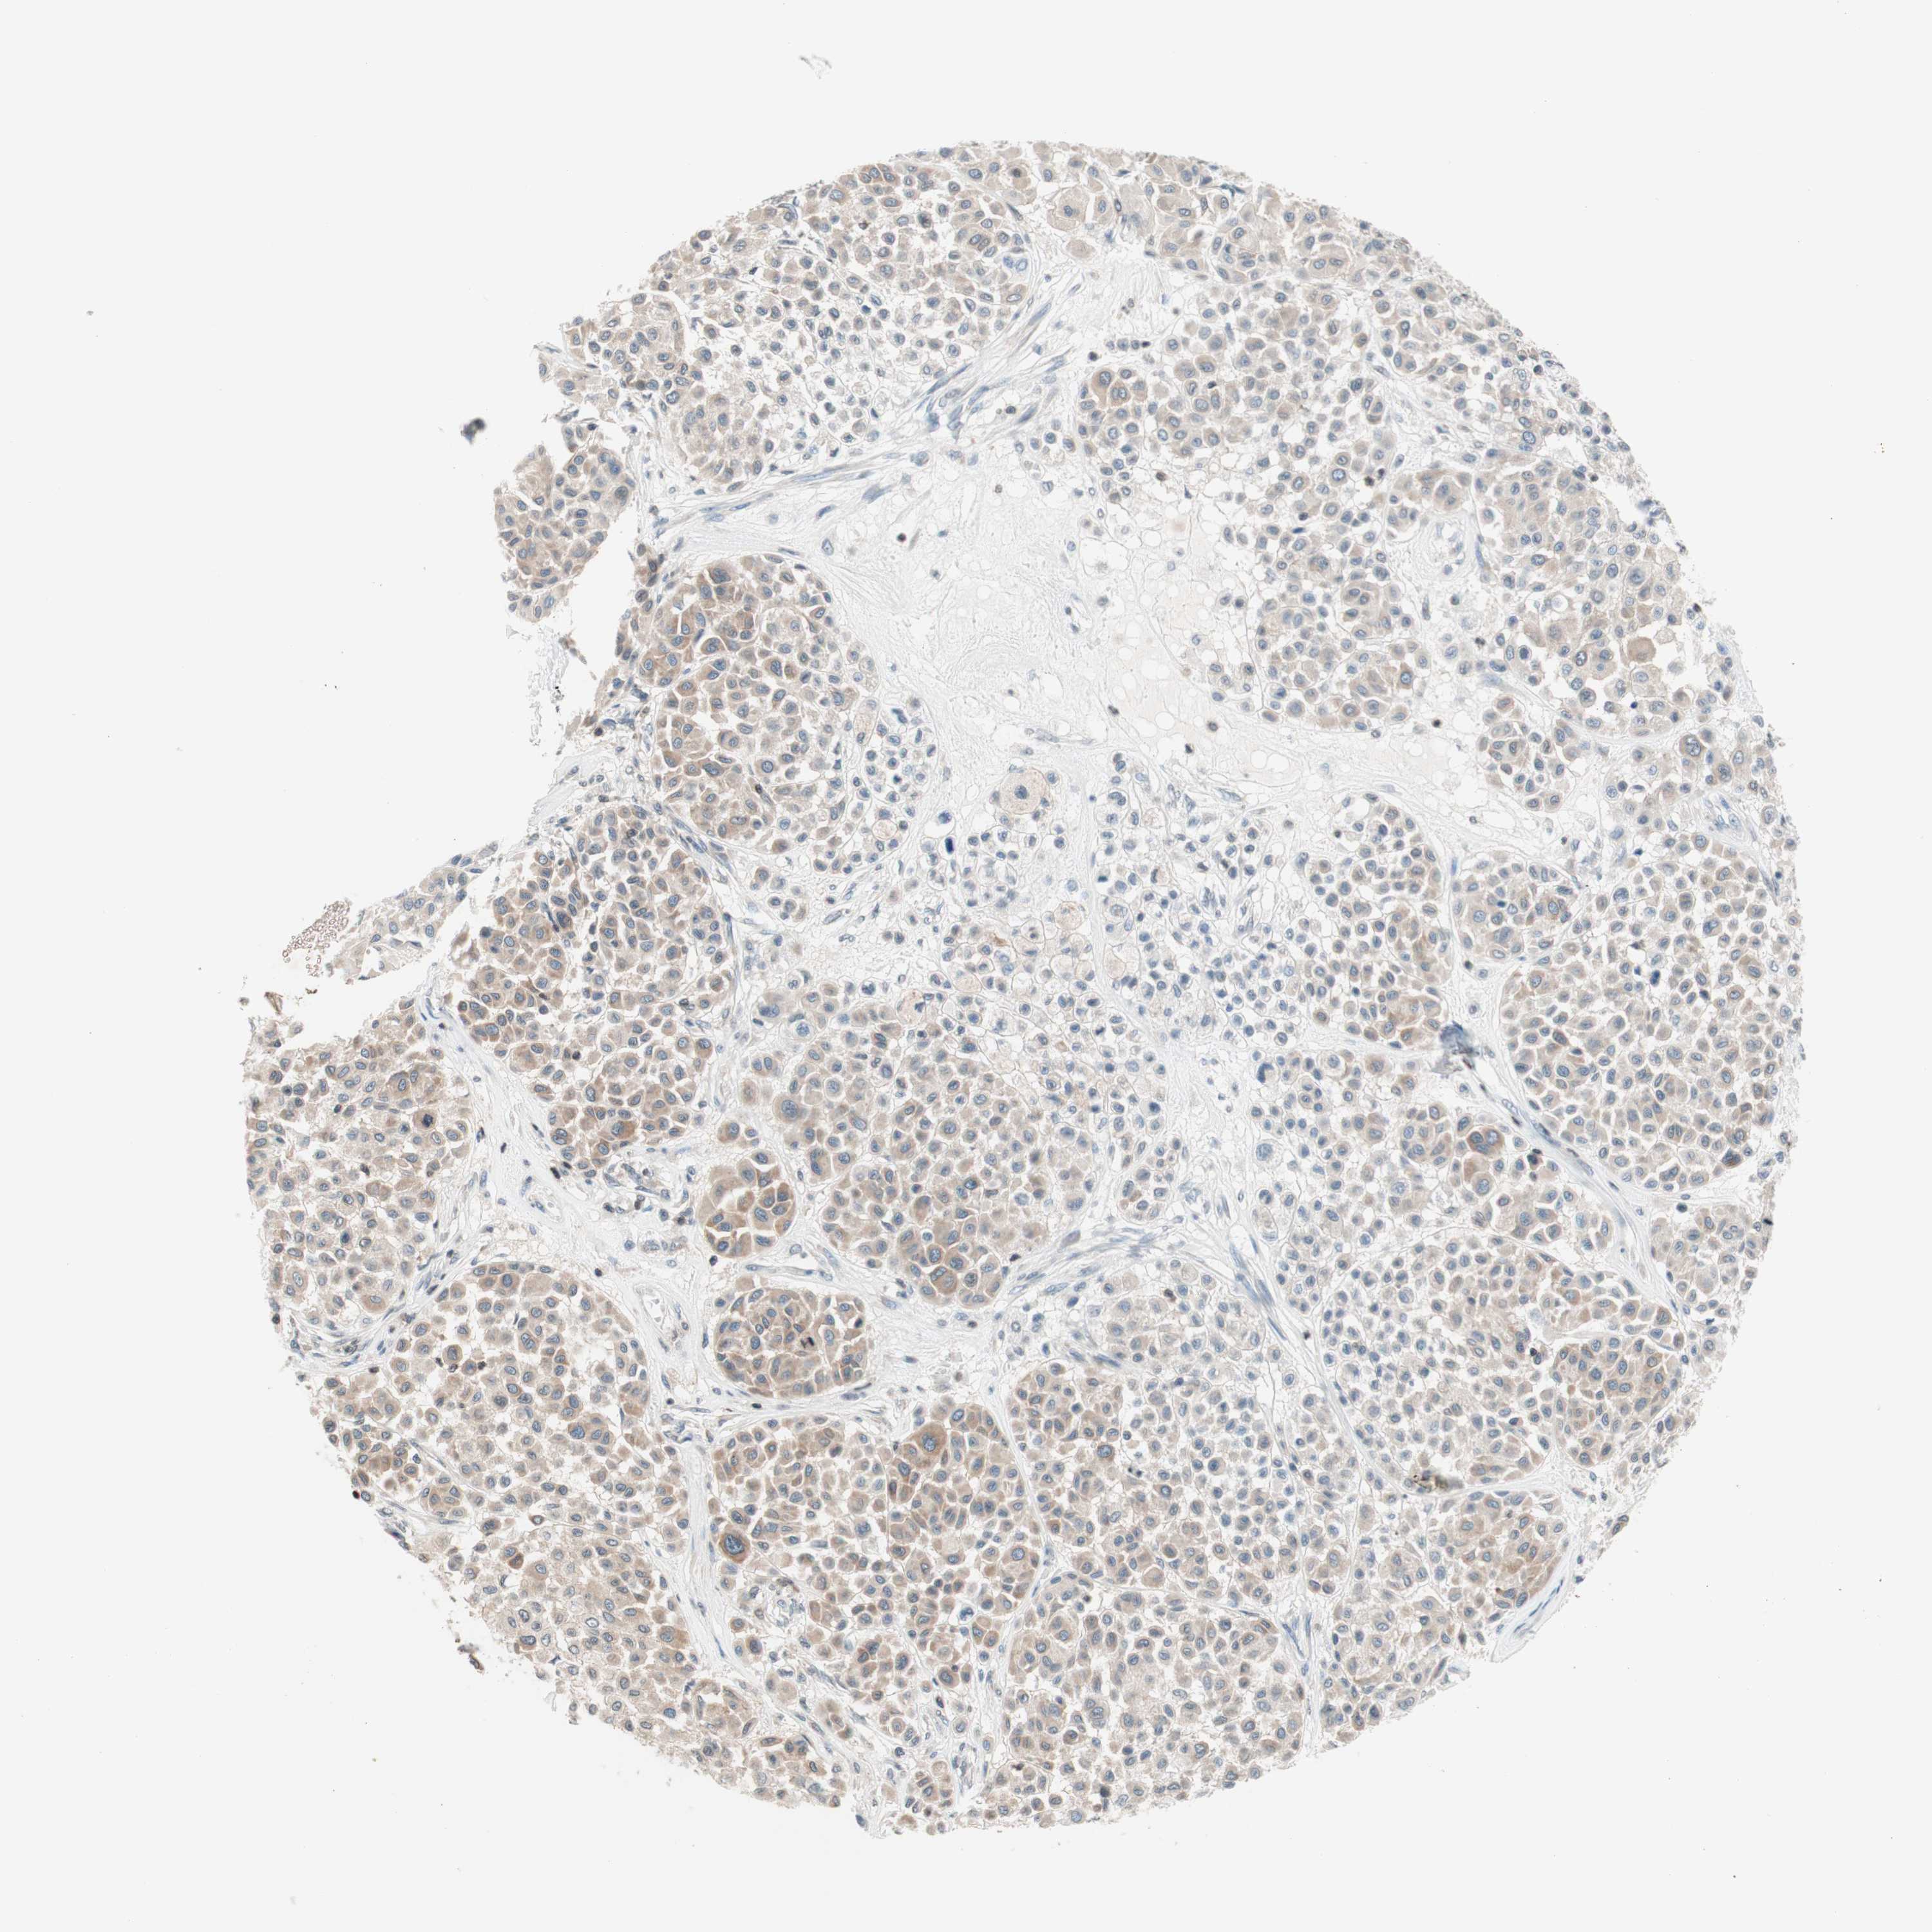

MELANOMA - Protein expressioni

A mouse-over function shows sample information and annotation data. Click on an image to view it in a full screen mode. Samples can be filtered based on level of antibody staining by selecting one or several of the following categories: high, medium, low and not detected. The assay and annotation is described here.

Note that samples used for immunohistochemistry by the Human Protein Atlas do not correspond to samples in the TCGA dataset.

Antibody stainingi

Antibody staining in the annotated cell types in the current human tissue is reported as not detected, low, medium, or high, based on conventional immunohistochemistry profiling in selected tissues. This score is based on the combination of the staining intensity and fraction of stained cells.

Each image is clickable and will lead to virtual microscopy that enables deeper exploration of all samples and also displays staining intensity scores, fraction scores and subcellular localization as well as patient and tissue information for each sample.

Antibody HPA003739

Staining

High

Medium

Low

Not detected

Intensity

Strong

Moderate

Weak

Negative

Quantity

>75%

75%-25%

<25%

None

Location

Nuclear

Cytoplasmic/membranous

Cytoplasmic/membranous,nuclear

Malignant melanoma, NOS